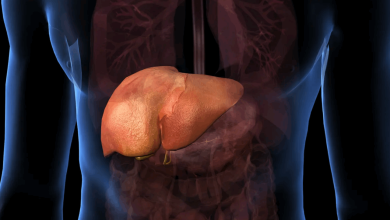

أمراض الكبد

هذا البلد يوافق على أول دواء لعلاج إحدى أمراض الكبد الحادة!

هذا البلد يوافق على أول دواء لعلاج إحدى أمراض الكبد الحادة! أجازت السلطات الصحية الأميركية الخميس أول علاج للشكل…